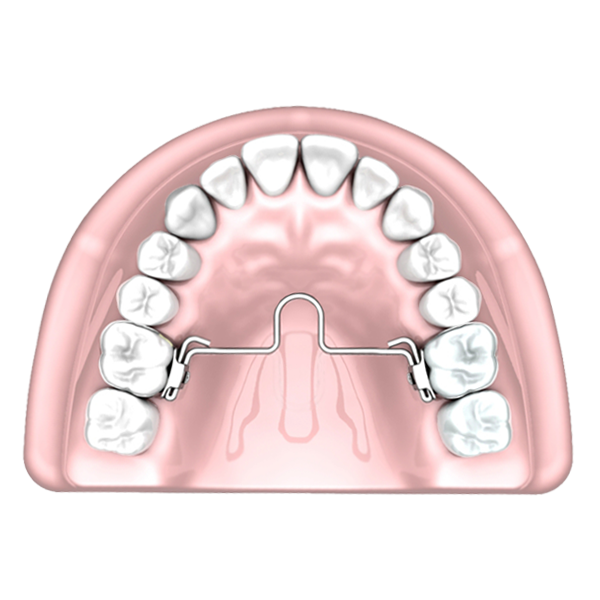

Morelli Palatal Bar With Mesial Loop is a device that connects to the first molar by lingual tubes. Made with wire 0.9 mm presented in versions with loop mesial or distal. Used to generate giroversion, intrusion, or torque forces, and to serve as a reinforcing anchorage.

- Correction of rotation, torque, or inclination of molars.

- Distalization of molars (associated with an anchoring system).

- Anchoring aid;

- First molar eruption control - relative intrusion.

- Expansion or contraction of the upper posterior segment.